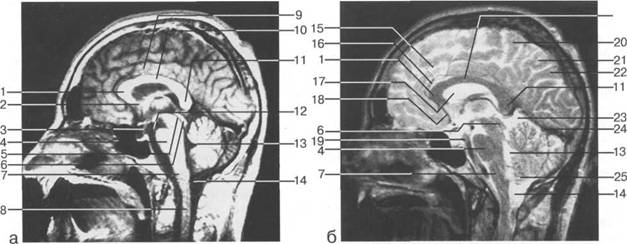

Задняя череп 13513u2010n 85;ая ямка представляет собой часть основания череп 13513u2010n 72;, ограниченную централь

Следует отметить, что в настоящее время оптимальным методом исследования структур задней череп 13513u2010n 85;ой ямки является МРТ, которая, в отличие от КТ, лишена артефактов от кост

Мозжечок заполняет практически весь объем задней череп 13513u2010n 85;ой ямки. Его поперечный раз

височная доля; 17 - полушарие мозжечка; 18 - |

Следует остановиться на анатомии подпаутинных пространств задней череп 13513u2010n 85;ой ямки IV 20 мм. Между основанием череп 13513u2010n 72; и нижней поверхностью мозга от большого затылочного отверстия вдоль ската и спинки турецкого седла простирается задняя базальная цистерна. В зави IV